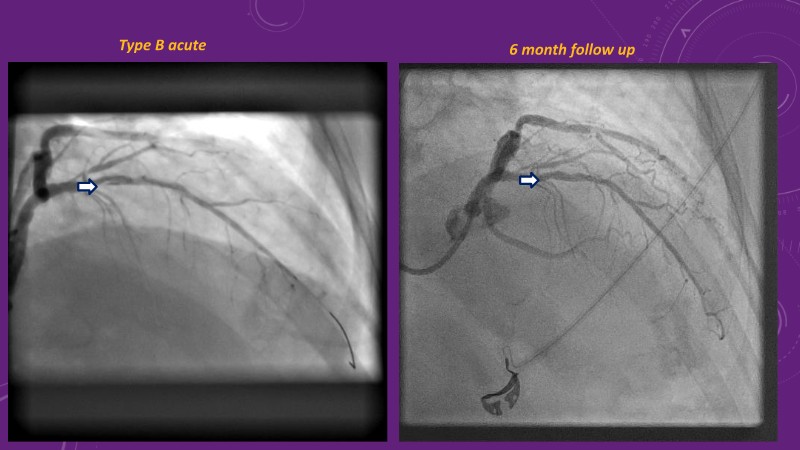

Explore cutting-edge strategies for optimizing drug-coated balloon (DCB) procedures in this session. Uncover practical tips to improve outcomes, review key indications, and examine international consensus on DCB use. Case presentations and expert discussions offer insights to refine your approach.